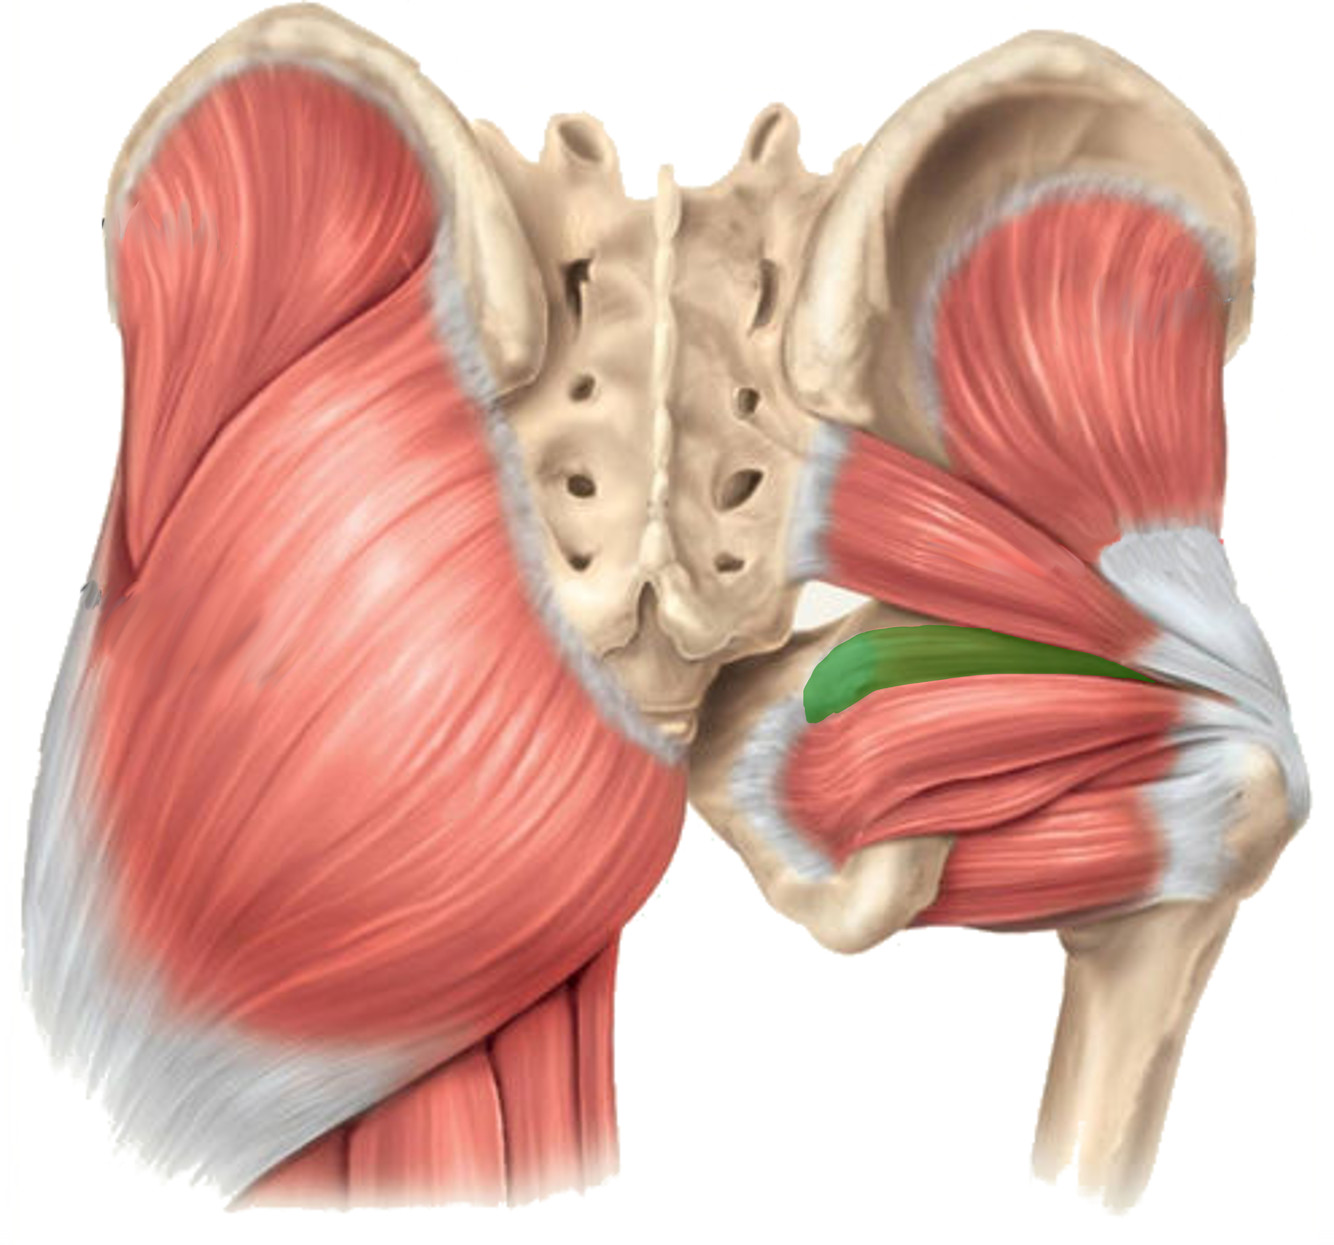

What is the innervation of this muscle (nerve roots)?

Muscle - Obturator internus

L5 + S1